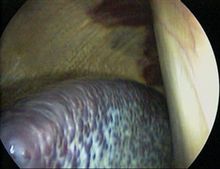

脾臟在活體時為暗紅色,上緣較銳,有2-3個切痕,而下緣則相對鈍厚。脾質脆而軟,受暴擊後易破碎。成人的脾臟重約150-200克。正常情況下,脾無法被觸及,腫大的脾則容易被觸到。